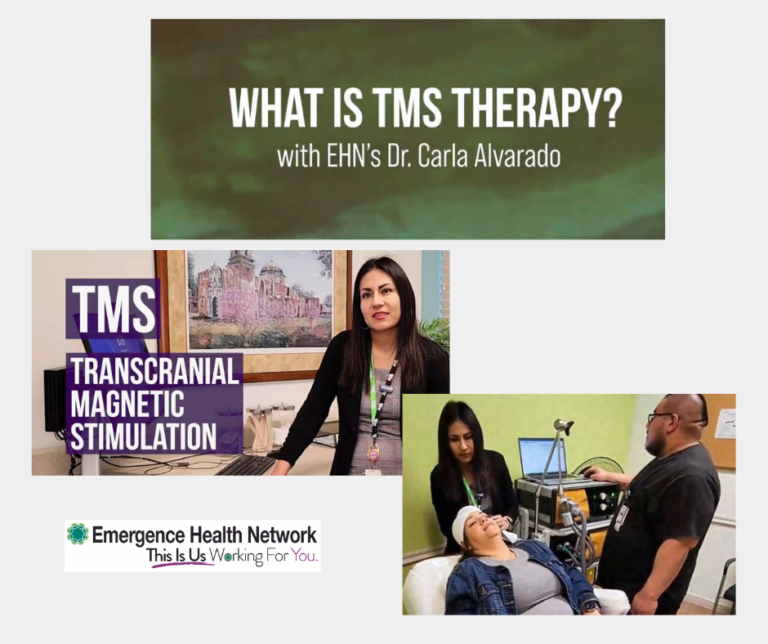

TMS Depression Therapy

EHN offers Transcranial Magnetic Stimulation (TMS) Therapy for Depression. Click the Read More Button for access to a short video that will help you better understand the benefits and what to expect during a treatment session.